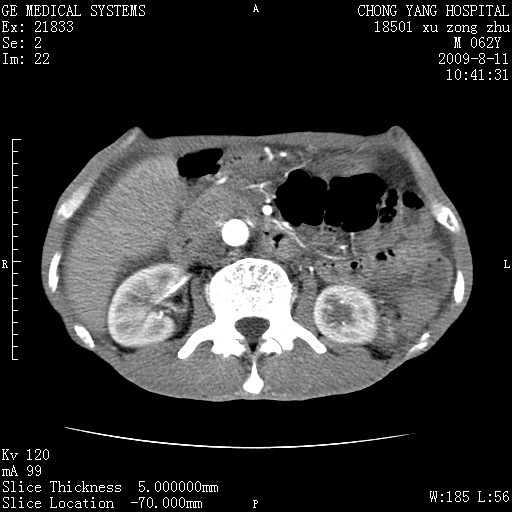

以下是引用杀毒软件在2009-8-11 16:35:00的发言:[br]肝内胆管扩张局限于左叶,胆管内有结石伴肝外胆管结石,胆管壁增厚呈弥漫性并发腹腔积液,胰腺边界模糊。[br][br]考虑---胆总管及肝内胆管结石继发胆管炎及胰腺炎,左肾下极囊肿,腹水。

以下是引用zjzjr在2009-8-11 17:35:00的发言:[br]肝内胆管扩张局限于左叶,胆管内有结石伴肝外胆管结石,胆管壁增厚呈弥漫性并发腹腔积液。[br][br]考虑---胆总管及肝内胆管结石继发胆管炎,左肾下极囊肿,腹水。